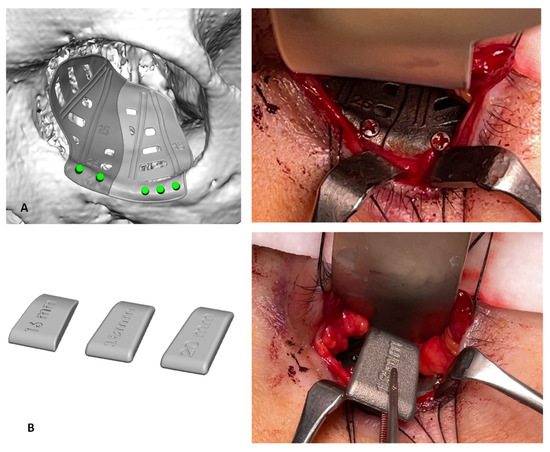

2. Case Report 1